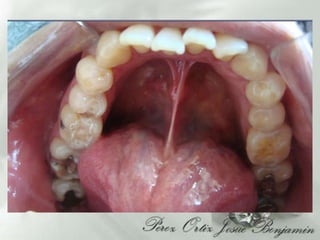

DIAGNOSTICOAparatos y sistemas:  Refiere :Antecedentes de Calculos Biliares , Intervencionquirugica aproximadamente hace 10 años    Bronquitis, aproximadamente hace 5 añosAntecedentes heredofamiliares 3 Hermanos con diabetes tipo II, Gingivitis Zona dientes anteriores inferioresLesiones cariosas grado I (24.25.27, 34)Restauraciones desajustadas (37,38,47,48,25, 26)  Oclusionismo  aproximadamente 15 años